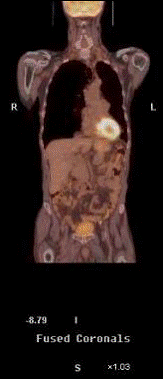

Fig. 7.

Rezulta ca PET si CT prezinta avantaje complementare, iar combinarea acestora crestepotentialul de localizare a leziunilor si reduce dificultatile de interpretare a imaginilor obtinute prin PET.

Fig. 8- Metastaze intrahepatice: imagini PET (18FFDG), CT si PET-CT.

sectiuni transversale (stanga) si sectiuni coronale (dreapta)